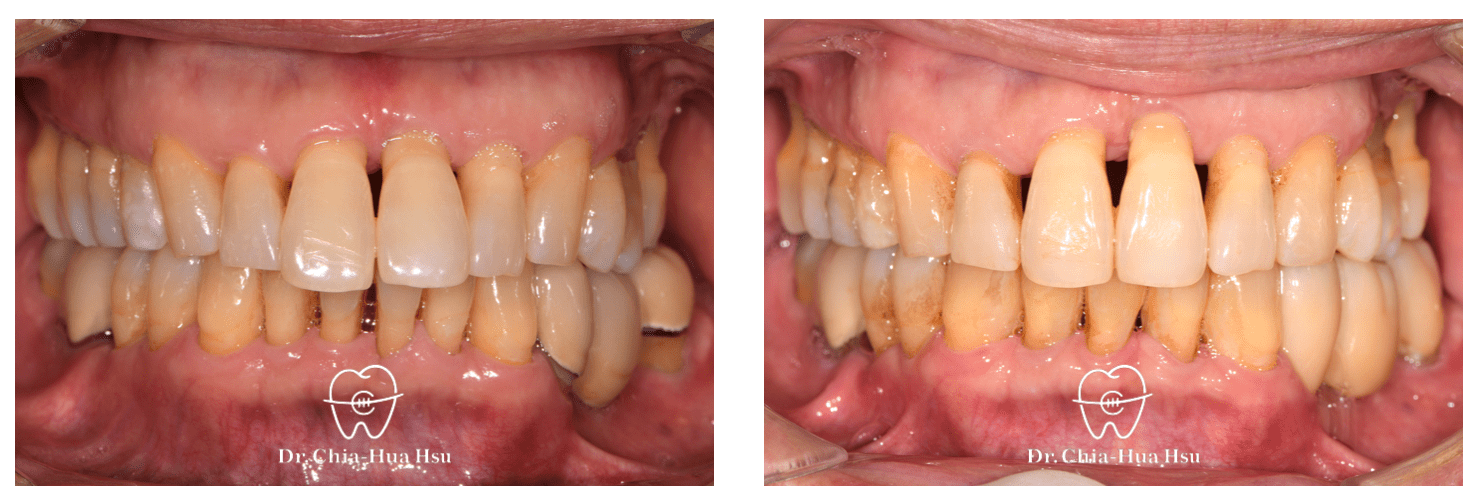

• 這位六十幾歲退休的先生,年輕時有做過矯正治療,年紀大了以後因為牙周病的關係牙齒又亂掉,因此來找許醫師做二次矯正治療。

• 病患主訴:在意暴牙和牙齒不整齊。

• 問題分析:患者除了暴牙、牙齒不整齊和黑三角縫明顯,還有牙周病的問題。

• 治療方式:在病患牙周治療結束後,與患者討論治療方案,最後使用對牙周健康友善的隱適美治療,並搭配上顎骨釘的使用,來改善患者的暴牙與齒列不正。後續也透過美學樹脂補牙來處理患者下顎門牙黑三角縫的問題。

• 治療時間:3 年 2 個月。

• 治療結果:在與牙周病科醫師、牙體復形科醫師的協同治療下,改善患者暴牙和齒列不正,恢復患者的牙周健康與美觀。

治療前

治療後